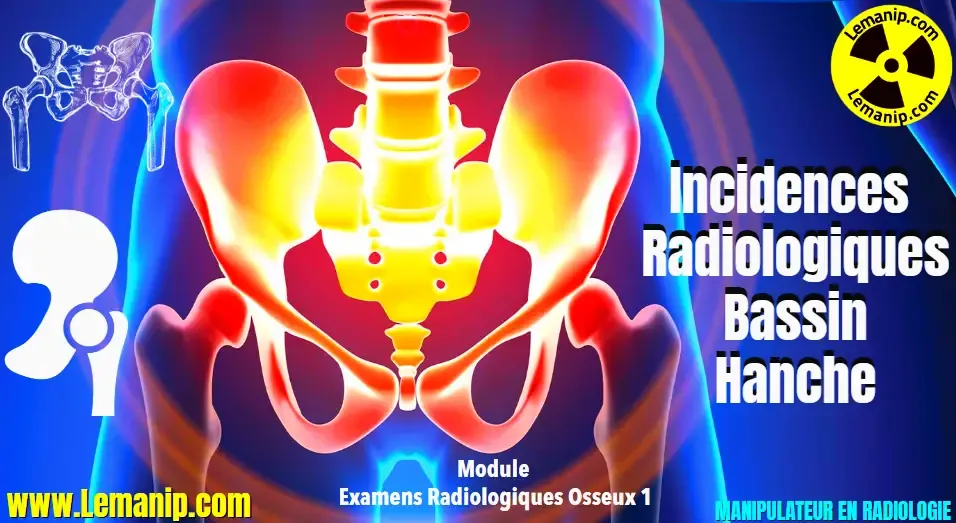

De plus, certains profils comme les joueuses féminines sont statistiquement plus sujets à ces blessures, en raison notamment de différences anatomiques et hormonales affectant notamment la laxité ligamentaire. La répétition des microtraumatismes et l’absence de récupération complète peuvent aussi fragiliser le ligament au fil du temps. Une identification précoce des signes cliniques comme une douleur intense, un gonflement rapide ou une sensation d’instabilité doit immédiatement orienter vers un diagnostic médical approfondi, incluant un examen clinique et souvent une IRM, référence pour vérifier un état normal des genoux ou la présence de lésions.

Lorsqu’une blessure au ligament croisé survient, une prise en charge médicale rapide et adaptée est primordiale. Le diagnostic repose sur un examen clinique approfondi, complété parfois par une imagerie comme l’IRM afin d’évaluer la gravité de la lésion. Le choix thérapeutique dépend de plusieurs paramètres : le degré de déchirure, l’âge du patient, son niveau sportif et ses attentes fonctionnelles.